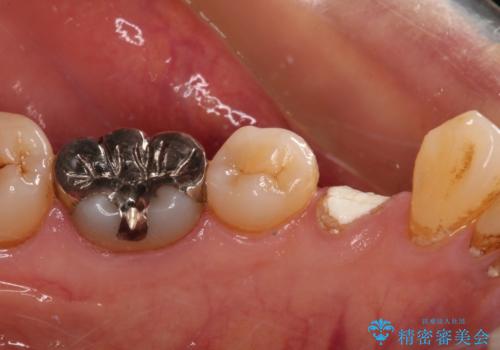

- 近医にて抜歯が必要と言われたとのことで来院された患者様です。

顕微鏡下で確認したところ、歯根に及ぶ破折線が認められたため、抜歯を行うこととしました。